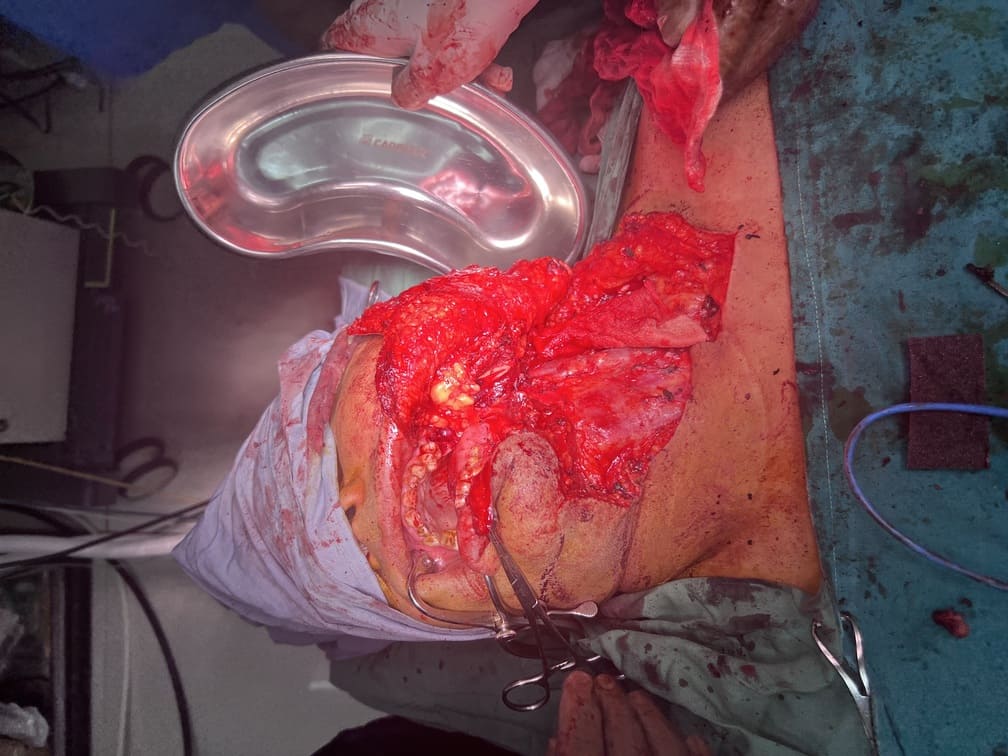

57 years old female suffering from left buccal mucosa growth involving left RNT and gingival surface of lip extending up to right angle mouth.left modified neck dissection with left distal segmental mandibulectomy with wide excision of left buccal mucosa with left RMT growth with excision gingival margin of lower lip with left pectoralis with right nasolabial flape done.

29-12-2025